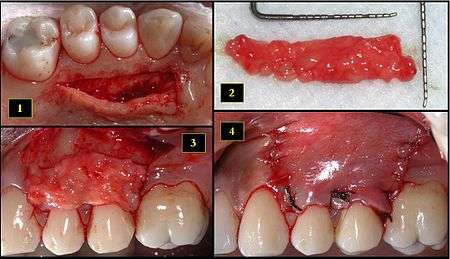

Subepithelial connective tissue graft

- Recipient site exhibits gingival recession on both premolars and first molar (molar recession is not an esthetic issue and will not be treated)

- Incisions prior to flap reflection

- Full thickness flap elevated

- Another viewpoint of the flapped recipient site

- Ipsilateral palatal mucosa serving as the donor site

- The retrieved connective tissue, approximately 25 × 6 mm in dimension

- Connective tissue placed at recipient site

- Recipient site flap coronally advanced and sutured to entirely cover the graft